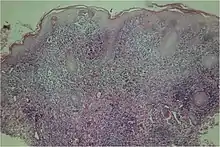

A microscopic examination of a biopsy of a yaw may show skin with clear epidermal hyperplasia (a type of skin thickening) and papillomatosis (a type of surface irregularity), often with focal spongiosis (an accumulation of fluid in specific part of the epidermis). Immune-system cells, neutrophils and plasma cells, accumulate in the skin, in densities that may cause microabscesses.

Warthin-Starry or Levaditi silver stains selectively stain T. pallidum, and direct and indirect immunofluorescence and immunoperoxidase tests can detect polyclonal antibodies to T. pallidums. Histology often shows some spatial features which distinguish yaws from syphilis (syphilis is more likely to be found in the dermis, not the epidermis, and shows more endothelial cell proliferation and vascular obliteration).[2]